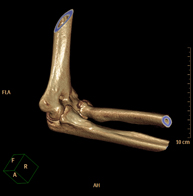

- Elbow CT

Radiological examination based on an X-ray system and detectors that rotate around the patient, reconstructing the images by computer (multidetector computed tomography - MDCT) to study the bones, muscles and joints of the elbow.